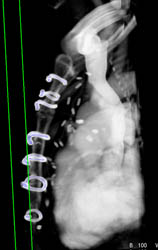

Dislocated Left Hip Prosthesis